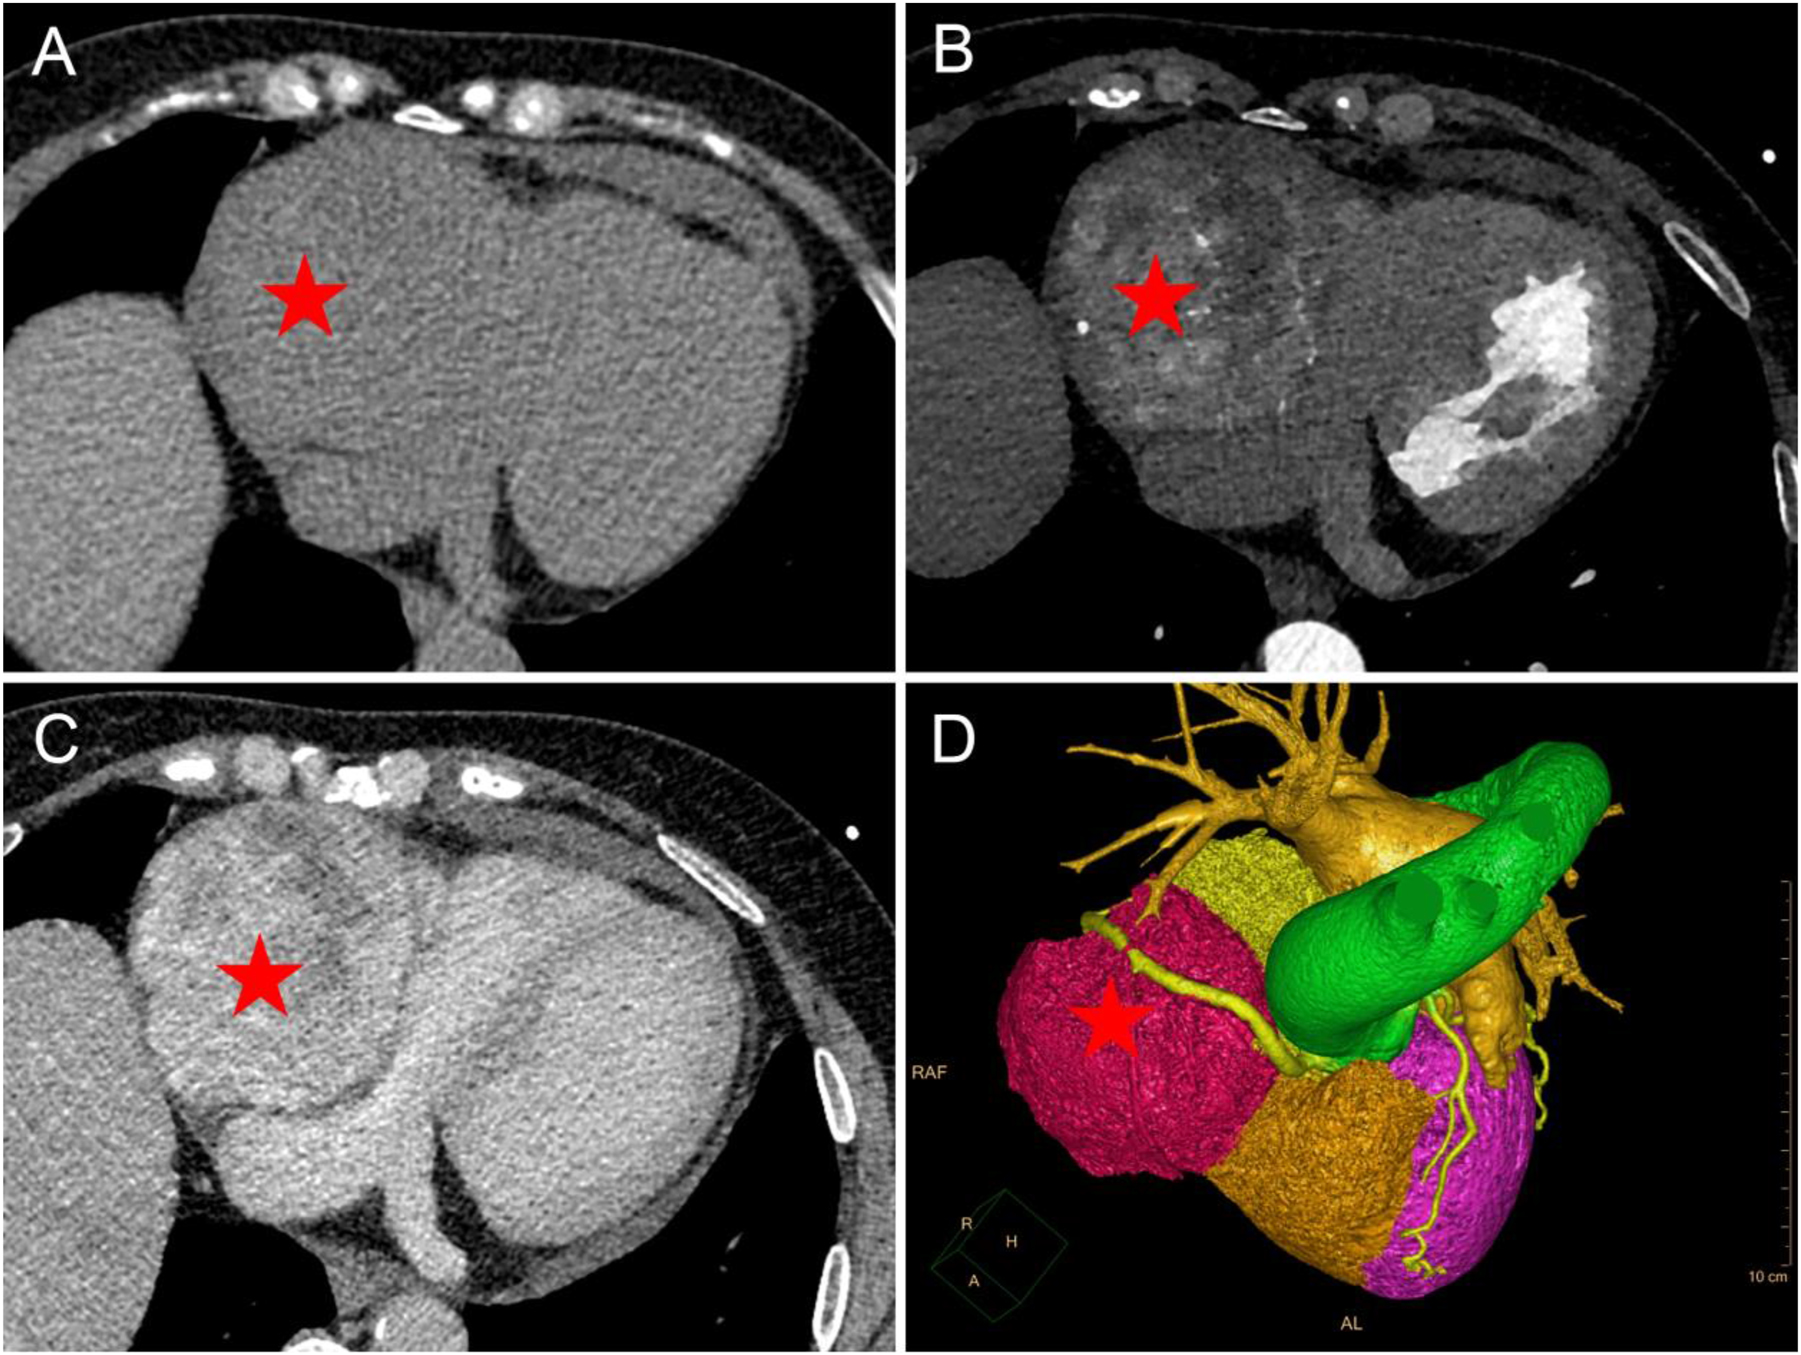

There was no history of hypertension, and no abnormalities were found on physical examination. Biochemical tests revealed an elevated B-type natriuretic peptide (BNP) level of 104.22 pg/mL. Bilateral carotid artery and bilateral lower extremity arteriovenous Doppler ultrasound results were normal (right femoral vein internal diameter of 9.7 mm and left femoral vein internal diameter of 9.2 mm). Echocardiography revealed a mass approximately 8.1×7.9 cm with a lower echo than the liver on the right lateral aspect of the heart that was regular and well defined, had an intact envelope, and no apparent colored blood flow within the mass. The mass caused a compression of the right atrium, which measured approximately 22 mm in transverse diameter. Furthermore, the internal diameter of the inferior vena cava at the entrance of the right atrium was approximately 10.6 mm, and the internal diameter of the inferior vena cava in the intrahepatic segment was approximately 15.8 mm. Based on ultrasound, the patient was diagnosed with an intrapericardial occupying lesion (Figure 1, Supplementary Video 1). A CT scan of the chest revealed a soft tissue mass adjacent to the right atrium causing significant compression and deformation of the right atrium and ventricle. After contrast administration, the mass showed apparent heterogeneous enhancement and multiple tortuous dilated vessels were seen within the mass. Coronary artery CTA showed a mass adjacent to the right atrium that was partially encircled by the right coronary artery (Figure 2, Supplementary Video 2). Cardiac MRI revealed a mass in the pericardium with hyperintensity on T2-weighted fat-suppressed (T2WI-FS) suppression imaging. The tumor was indistinguishable from the right heart, causing compression and deformation of the right heart. Cine MRI of the heart showed no significant myocardial thinning or thickening in the systolic or diastolic phases of the ventricle (Supplementary Video 3). The MRI suggested an intrapericardial occupying lesion between which an isolated fibrous tumor of epicardial or myocardial origin, hemangioma, or hemangiosarcoma was primarily considered (Figure 3). Since MRI suggests that the tumor is highly vascularized, the risk of bleeding after tumor biopsy is high. To assess the risk of bleeding after surgical removal of the tumor, the patient underwent coronary angiography. Coronary angiography revealed that the tumor received most of its blood supply from the right coronary artery.

Chest CT and coronary CTA findings of PGL. (A–C) Chest CT. A large mass similar in density to the liver (red pentagram) was seen adjacent to the right side of the heart, which was not clearly delineated from the right atrium and ventricle. CT attenuation was 34 Hounsfield units (HU) on non-enhanced CT ((A) non-enhanced CT). After contrast administration, the mass (red pentagram) was continuously and heterogeneously enhanced (B) arterial phase; (C) venous phase. (D) Volume rendering showed that the mass was partially surrounded by the right coronary artery, which was moderately displaced by the mass.